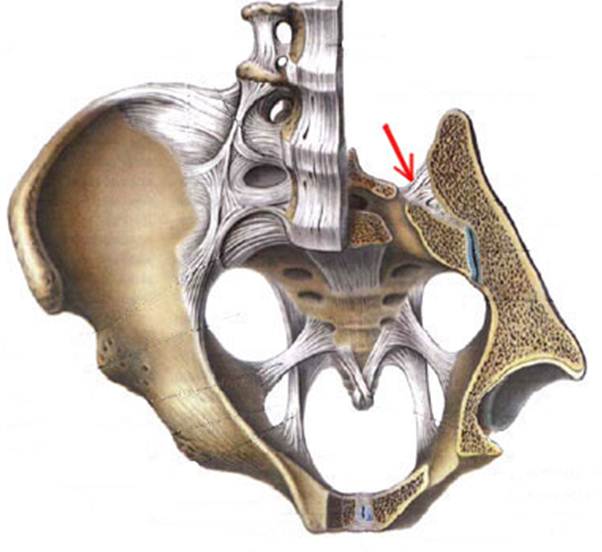

S: Стрелка указывает на art. sacroiliaca (латинский язык).

S: Стрелка указывает на lig. Sacroiliaca posteriora

S: Стрелка указывает на lig. Sacrococcygeum anterius